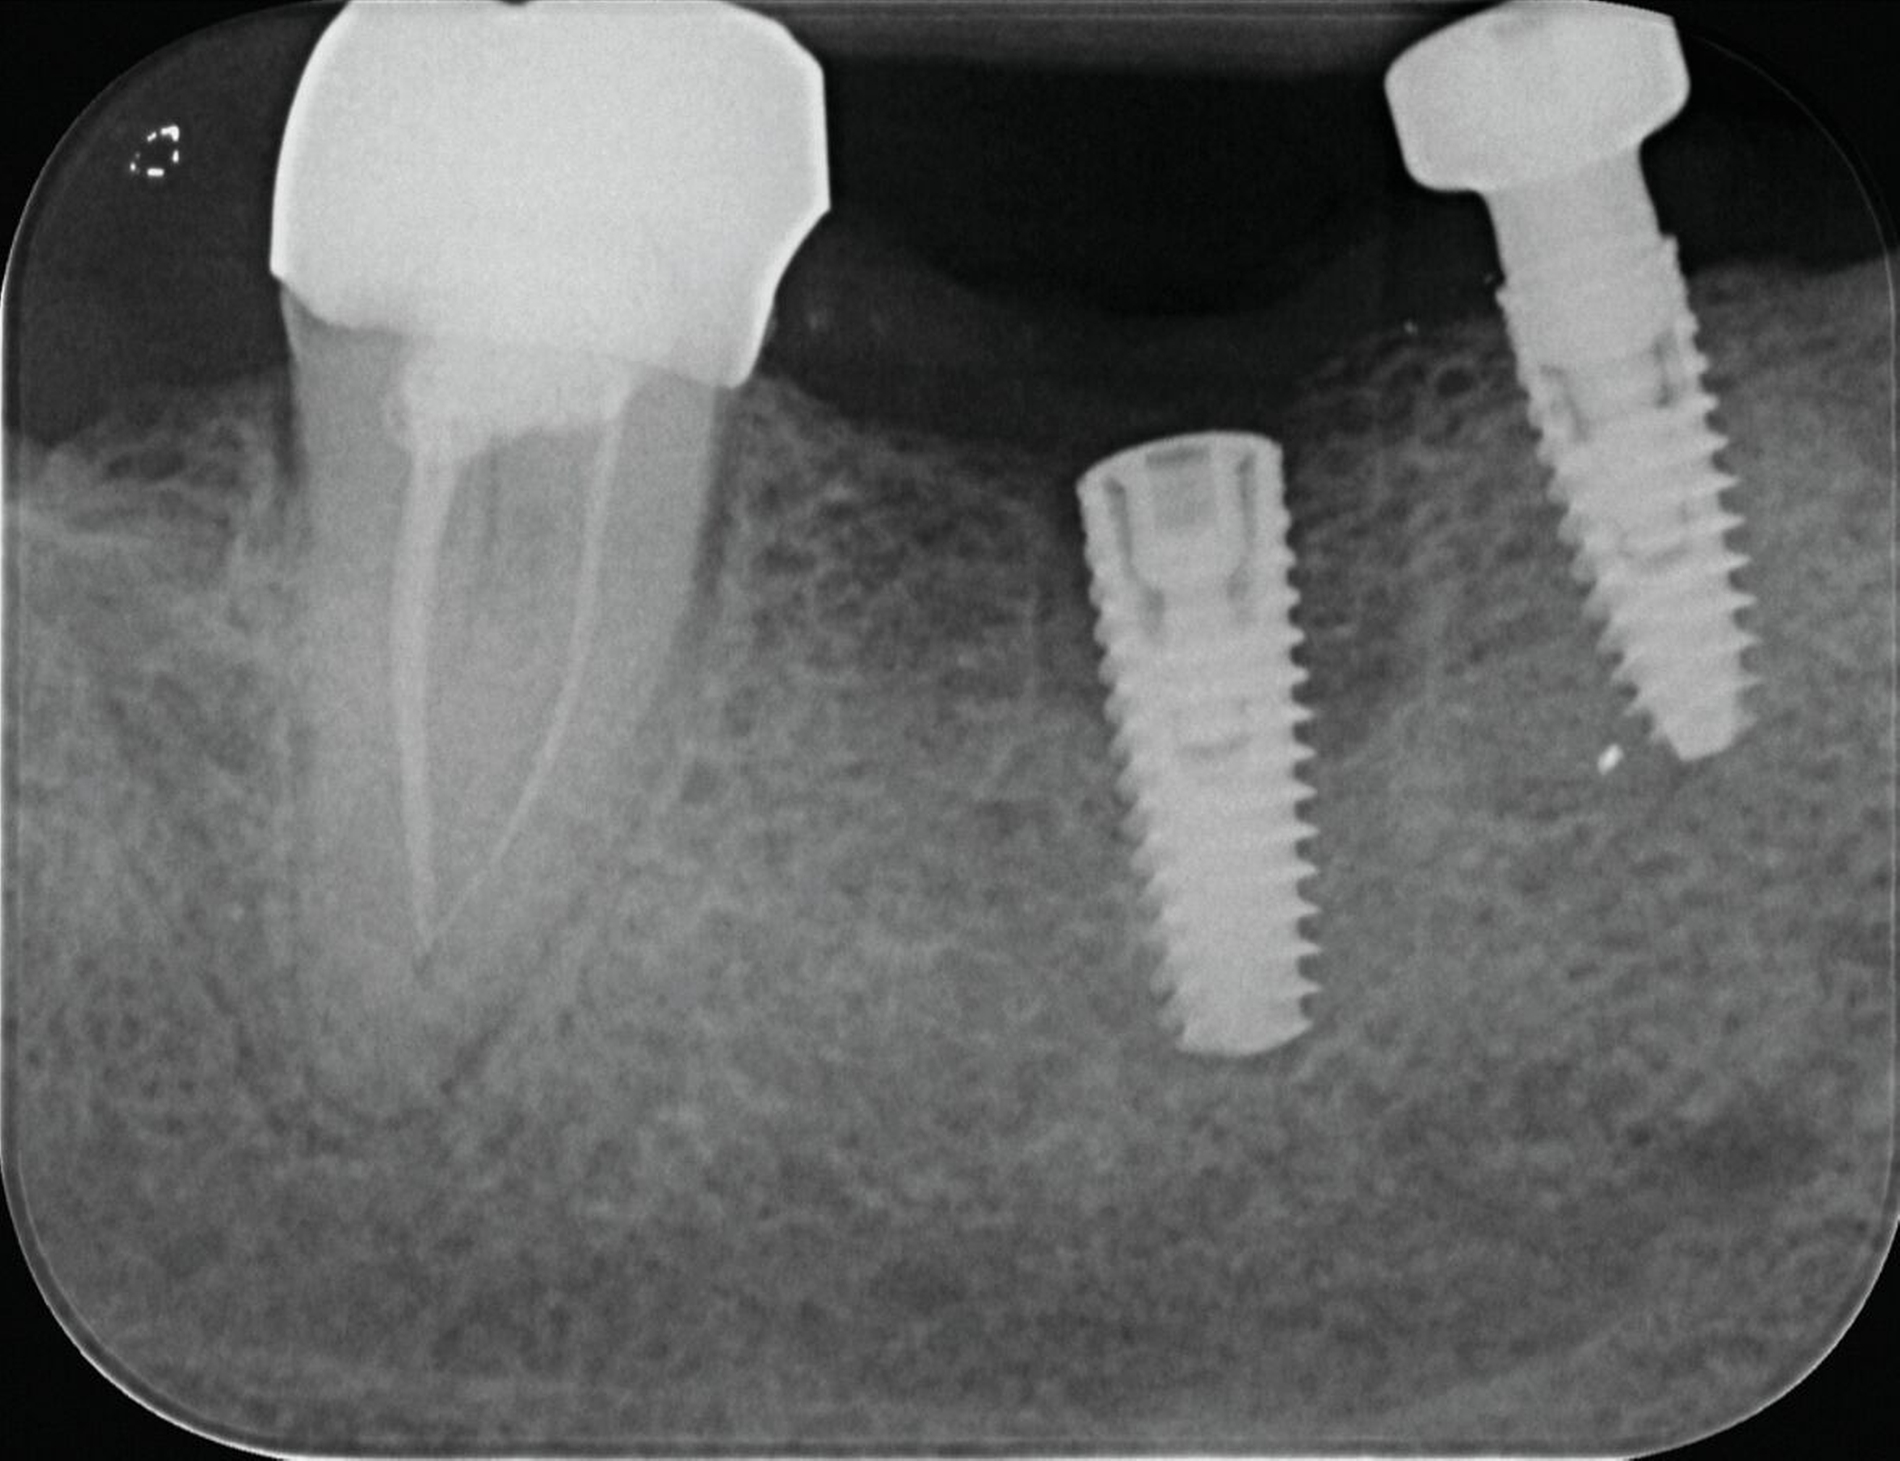

Im Implantatbereich regio 35 wurde eine abgebrochene Schraube diagnostiziert. Zum Zeitpunkt der Überweisung war die Integrität der Implantatschulter bereits kompromittiert, auch die Gewindegänge wiesen deutliche Schäden auf. Obwohl das Fragment radiologisch deutlich nach koronal überstand und somit zunächst als entfernbar erschien, zeigte sich bei der mikroskopischen Kontrolle, dass es fest auf dem Boden des Implantats aufsaß. Mehrere vorsichtige Mobilisationsversuche blieben erfolglos. Aufgrund der fortgeschrittenen Schädigung wurde das Implantat schließlich mithilfe einer passgenauen Trepanfräse entfernt und durch ein neues Implantat ersetzt (Abbildung 8).

Hier kam es zum Bruch des Gingivaformers während der Einheilphase. Das abgebrochene Schraubenfragment setzte sich im weiteren Verlauf auf dem Boden des Implantats ab. Vermutlich führte der Versuch, das Fragment mit einem Ultraschallinstrument zu mobilisieren, zu einer zusätzlichen Beschädigung des Innengewindes. Da alle konservativen Entfernungsversuche erfolglos blieben und die Wiederverwendbarkeit des Implantats nicht mehr gewährleistet war, wurde das Implantat entfernt und durch eine Neuimplantation ersetzt (Abbildung 9).